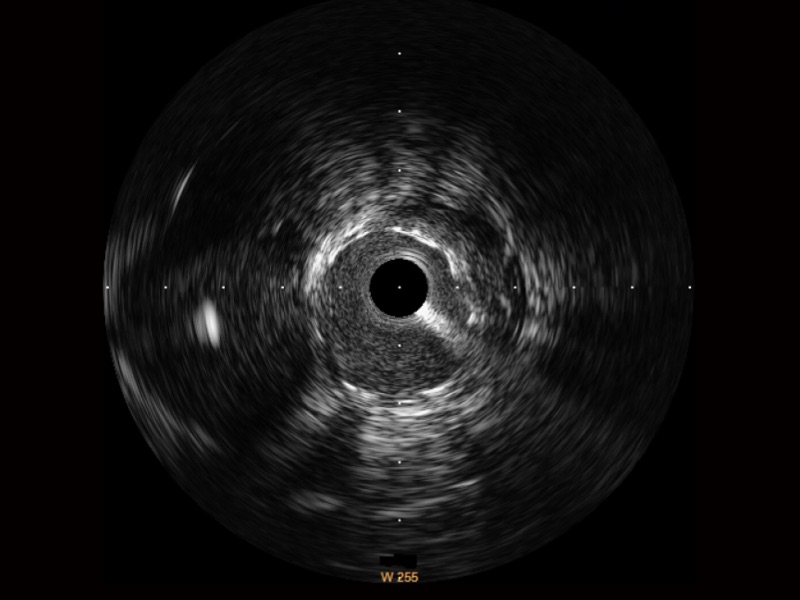

银河优越会宽频IVUS图像

对比传统IVUS导管成像,银河优越会宽频IVUS图像的近场支架梁显影更细腻,远场中膜外血管仍清晰可辨,兼顾远中近,兼顾分辨力与穿透深度